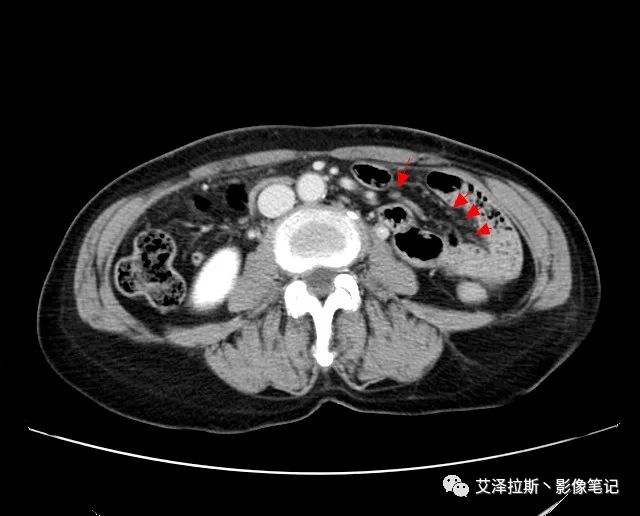

【影像所見】 胃竇部狹窄,胃壁環形增厚,小彎側見一巨大潰瘍,周圍伴“環堤征”,漿膜面不完整,胃周脂肪見網格狀條索影,病灶與肝臟左葉、胰腺鉤突脂肪間隙消失,增強掃描病灶明顯強化。引流區內約15個區域淋巴結受累。

【診斷意見】 胃竇部胃癌(T4N3期) 該病例腫塊突破漿膜層,與肝臟左葉、胰腺鉤突分界不清,脂肪界面消失,定為T4期; 受累及的淋巴結為15個區域,定為N3; 有無遠處轉移尚不明確,所以M期暫時無法確定。